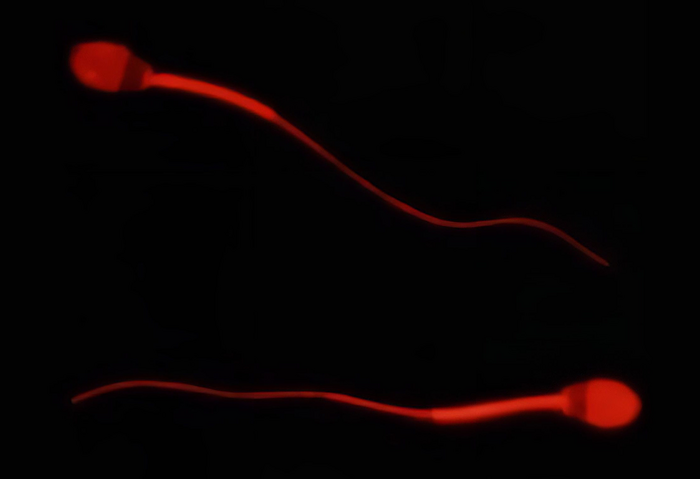

图:在母羊排卵当天,公羊的精子可以穿透宫颈粘液。

图片来源:Xavier Druart